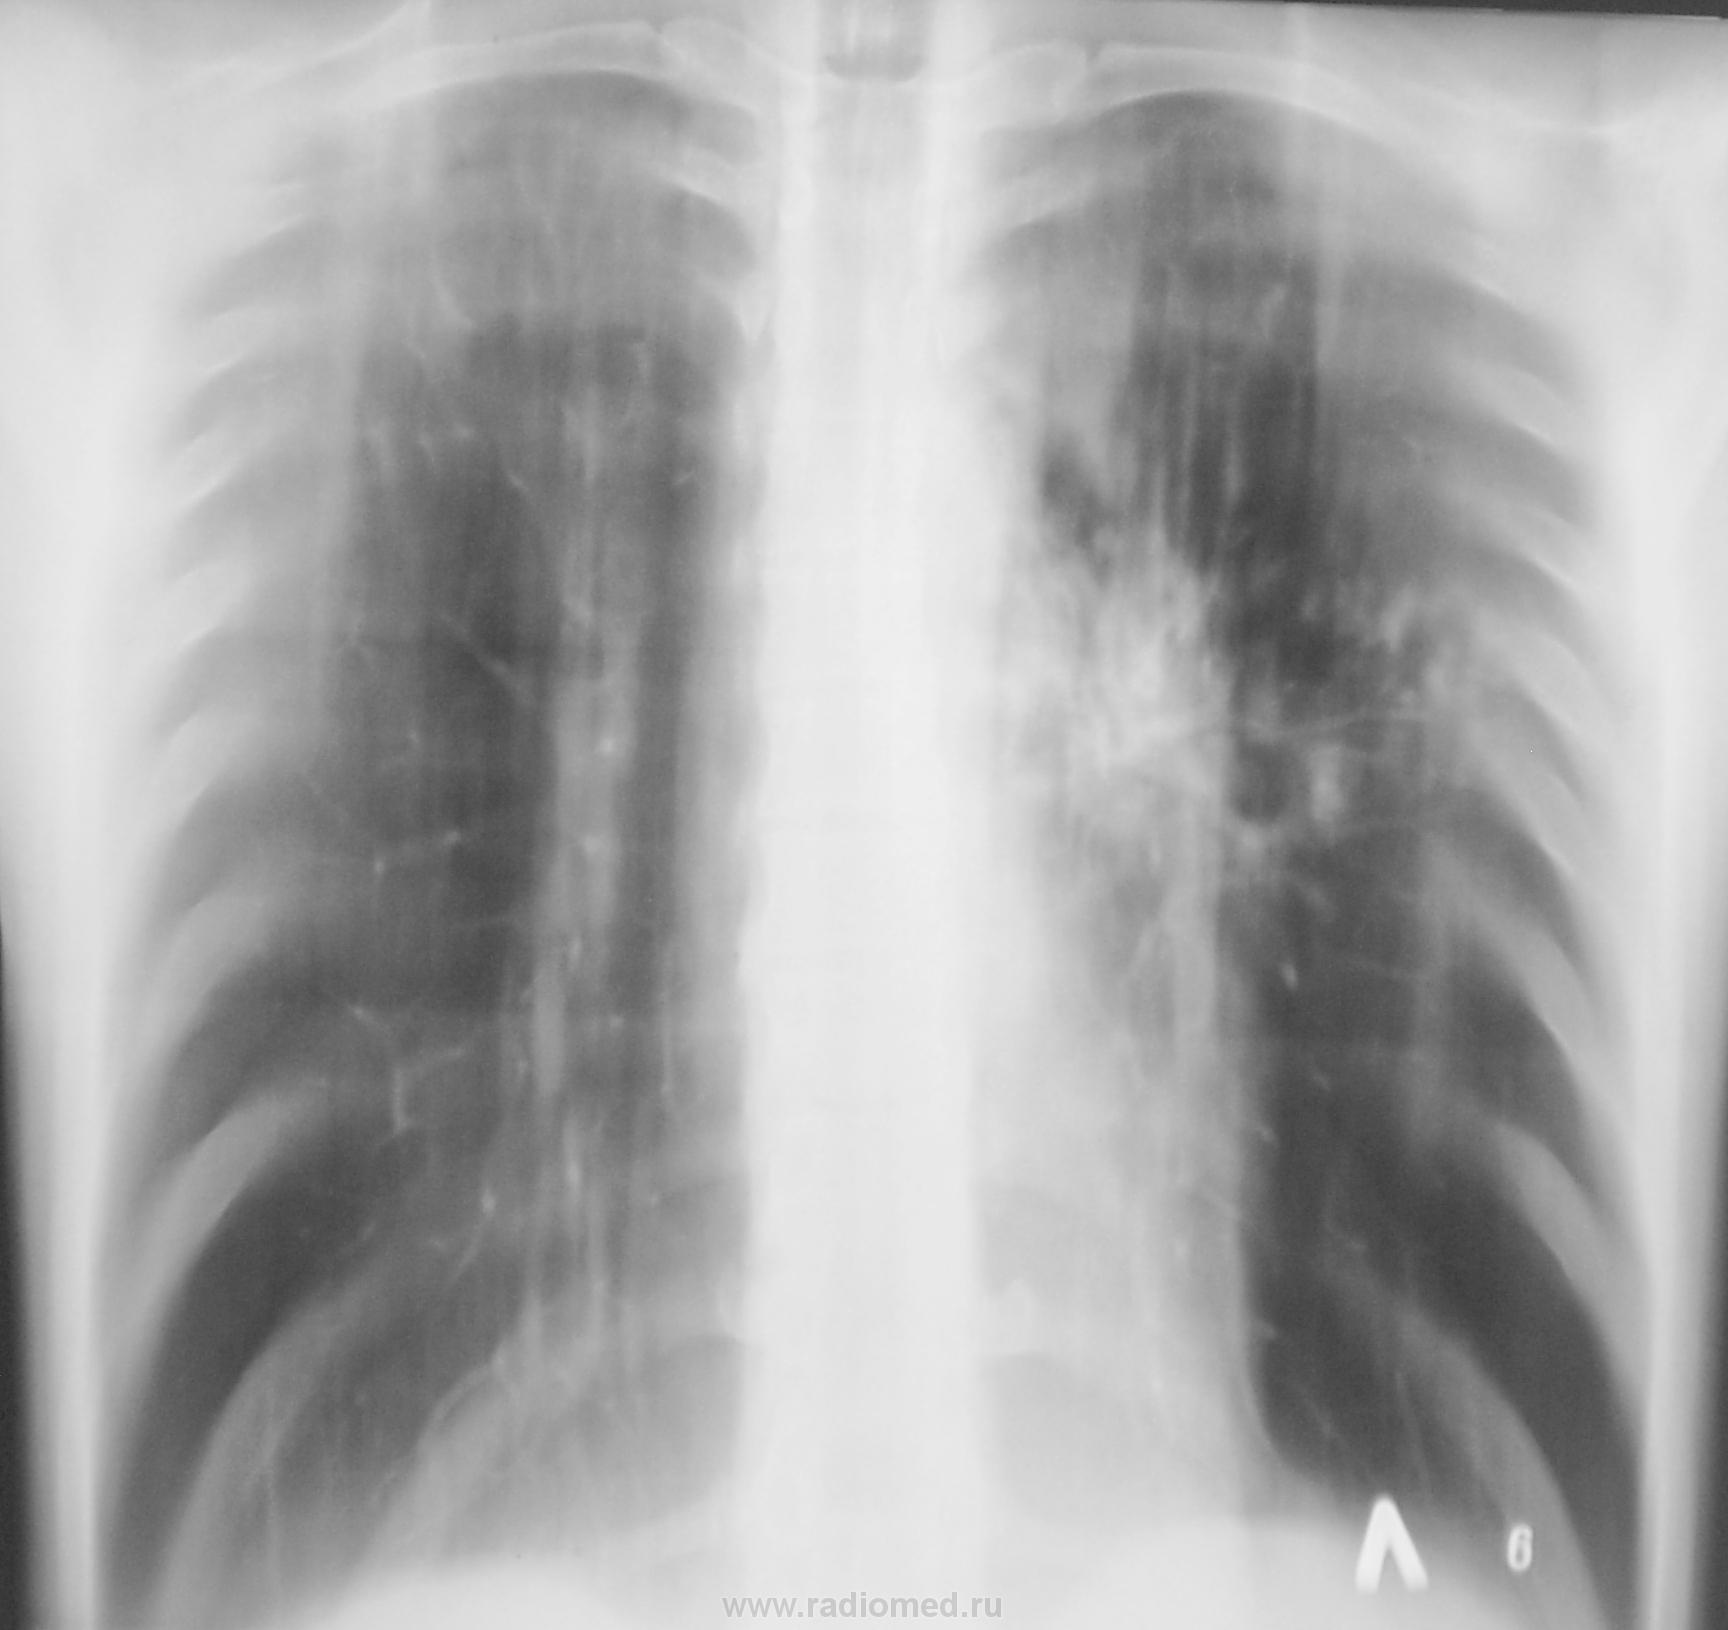

Динамика в процессе лечения.

Контроль еще через 1 месяц.